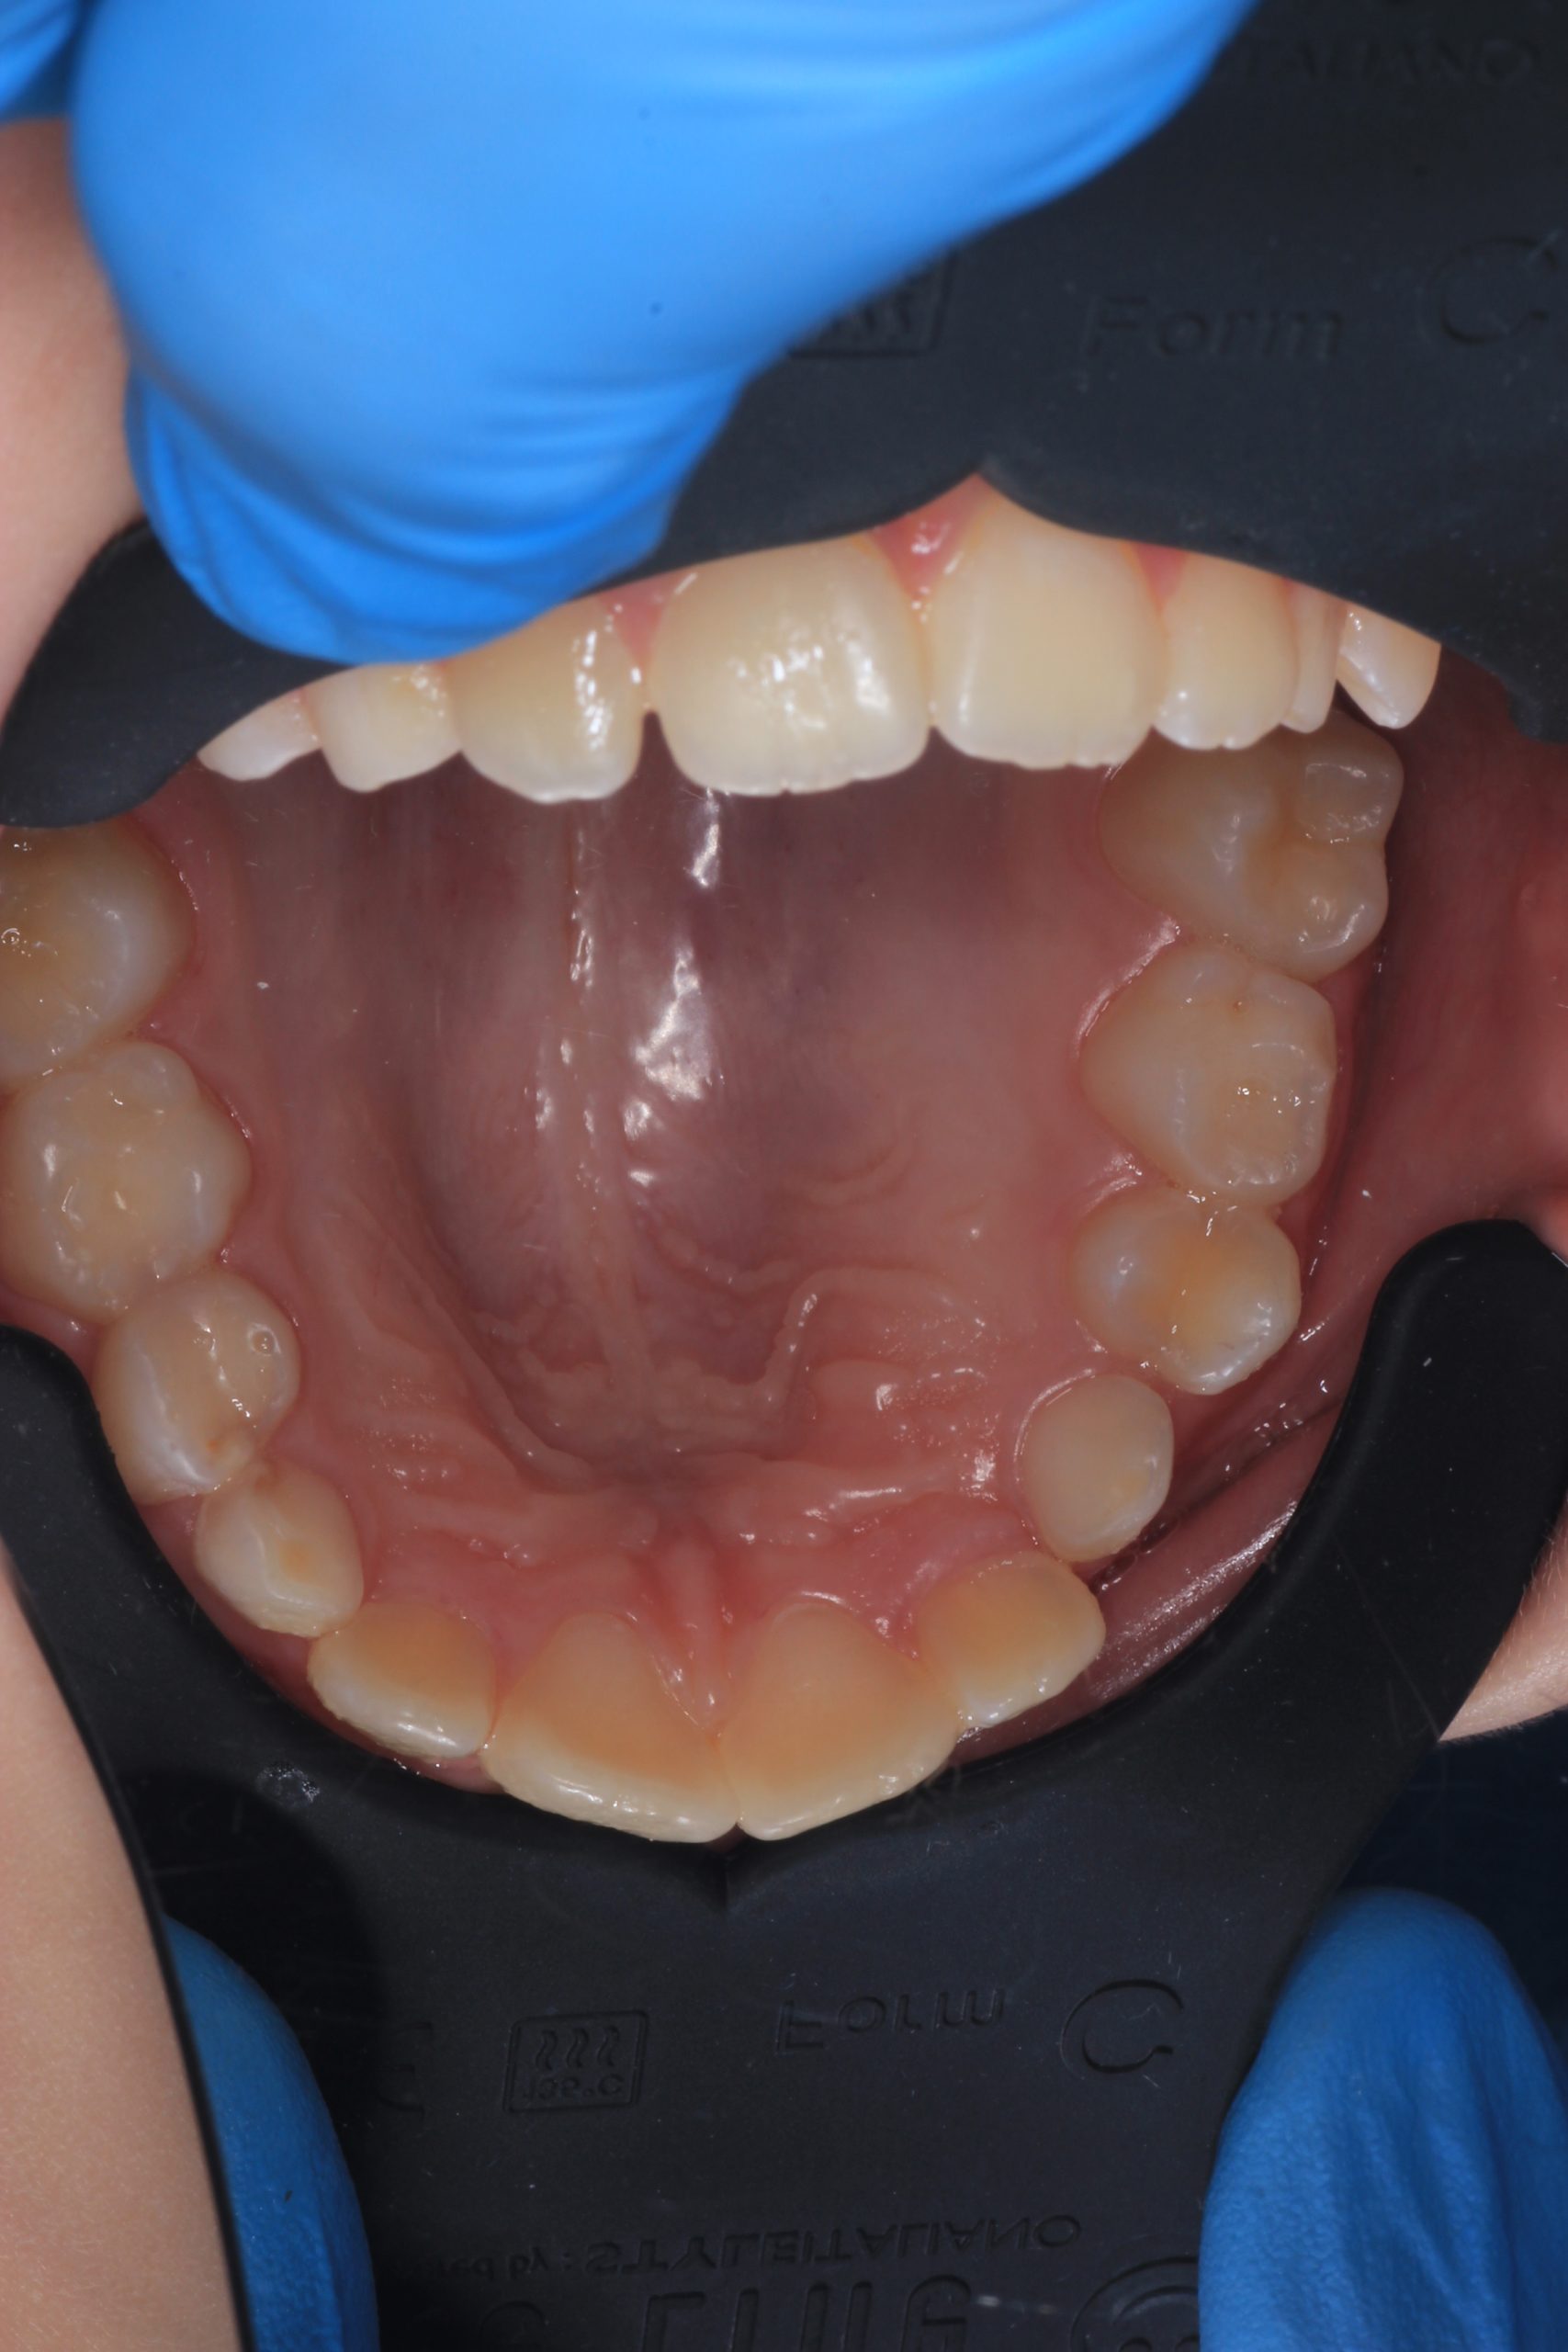

We examine the condition of teeth, gums, and bite. - Plaque Disclosure with Special Indicators

Areas that weren’t cleaned well appear purple. The darker the shade, the older the plaque. This helps both kids and parents understand where brushing needs to improve. - Brushing Training & Home Care Tools Selection